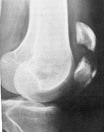

El Mundo de la RodillaRodilla.html